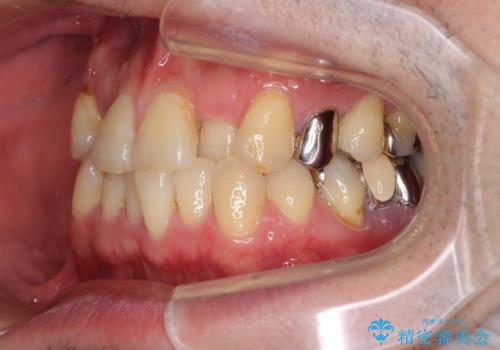

- 奥歯の痛みと前歯のデコボコを気にして来院された患者様です。

左右下顎の大臼歯は、ともに歯根が破折しており、抜歯が必要な状態でした。

咬み合わせは受け口傾向であり、上顎前歯の叢生が顕著であったことから、第1小臼歯抜歯による矯正治療も検討しましたが、下顎大臼歯を左右ともに抜歯するため、非抜歯による矯正治療を行うこととしました。